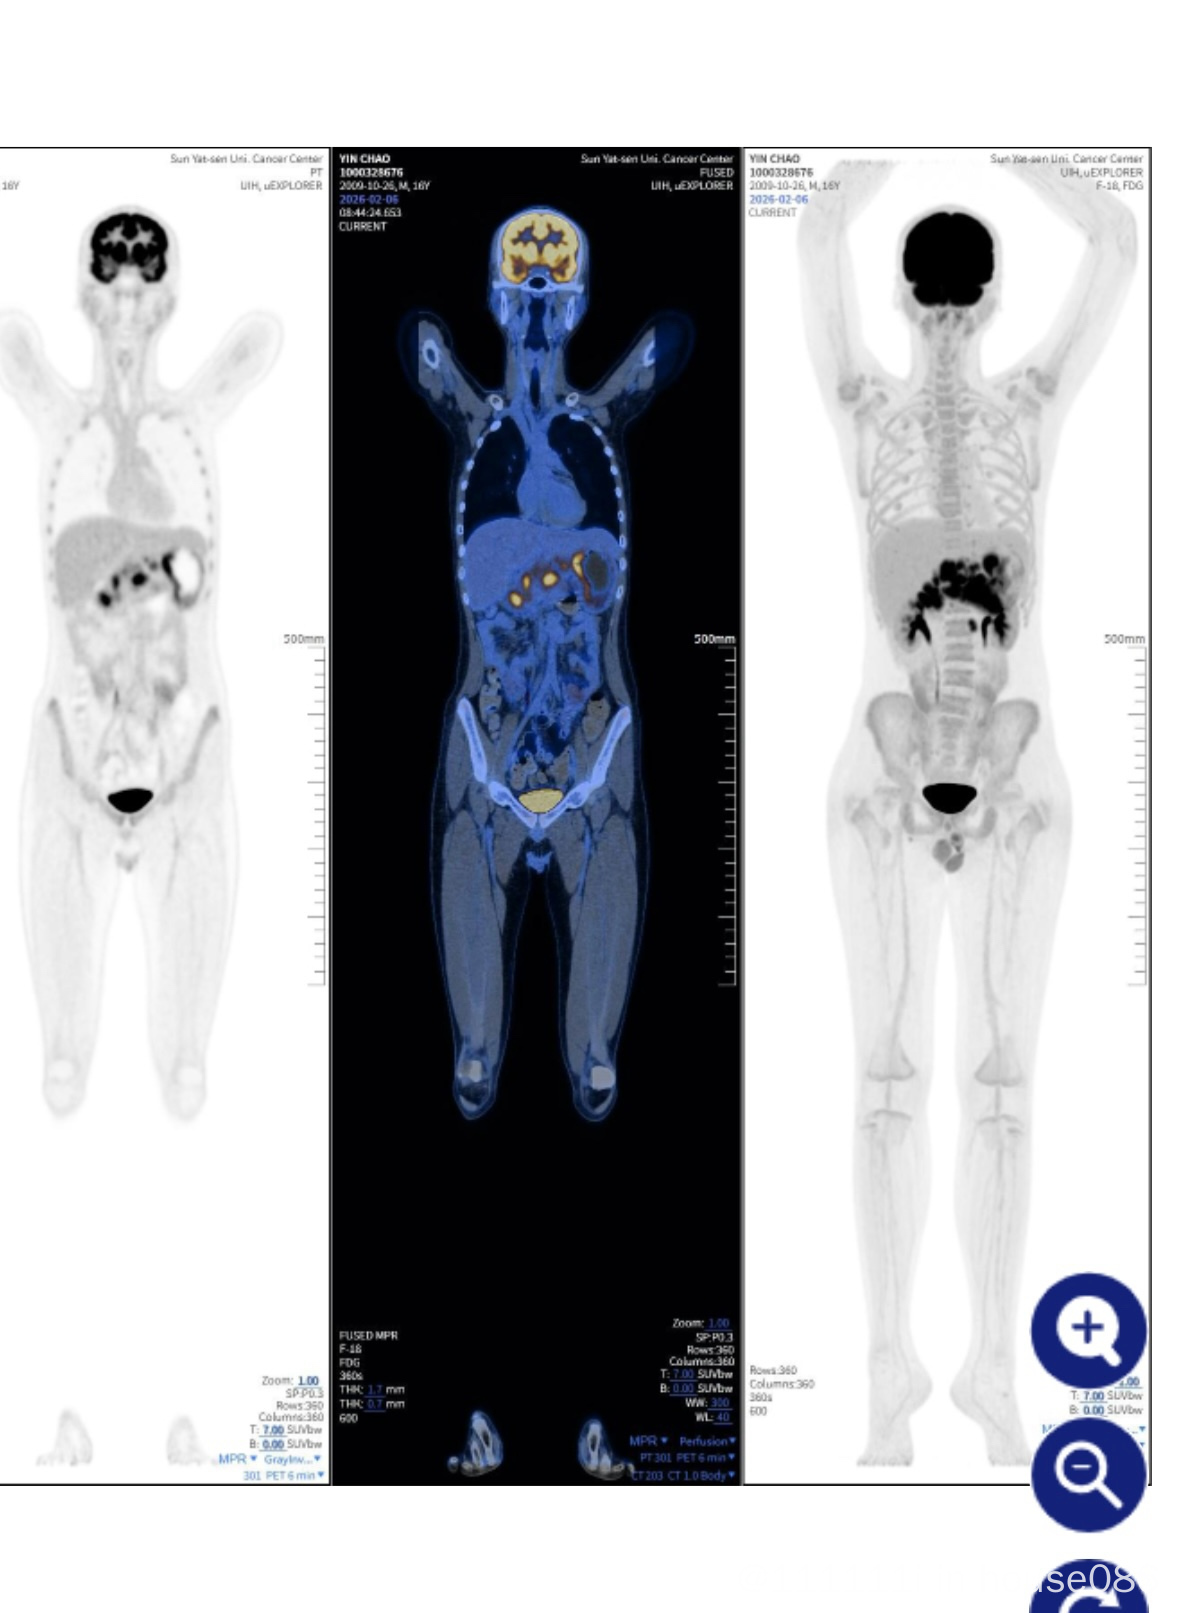

这是大概时间流程:1.21号照胃镜发现巨大胃溃疡,取活检送到中肿,2.5号病理说胃malt淋巴瘤,随后照了petct,发现腹部有浸润,之后腹部淋巴结穿刺,2.13号直接上了第一次化疗,使用的rcho,没有上激素,2.27号腹部穿刺结果出来了,是大b细胞淋巴瘤,骨髓未侵犯